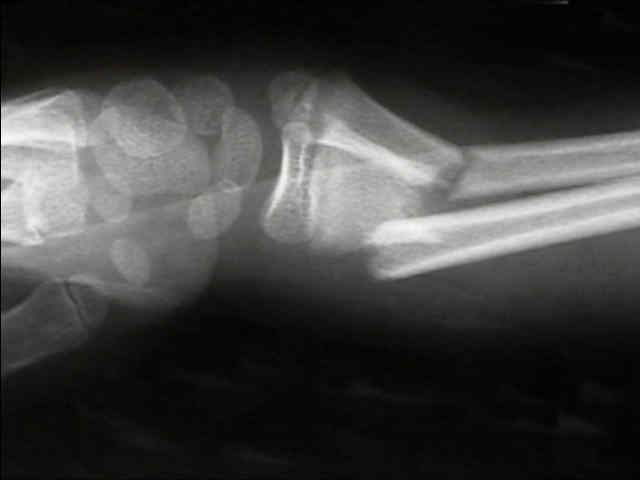

bayonette apposition

- generally bayonette opposition will require operative reduction (either closed with a Kapandji K wire levering technique or in some situations, an open reduction and fixation with K wires will be required);

- historically, overriding of a both bones forearm fracture was acceptable if...

- there was no deviation of radius and ulna toward each other;

- there was no encroachment of the interosseous space;